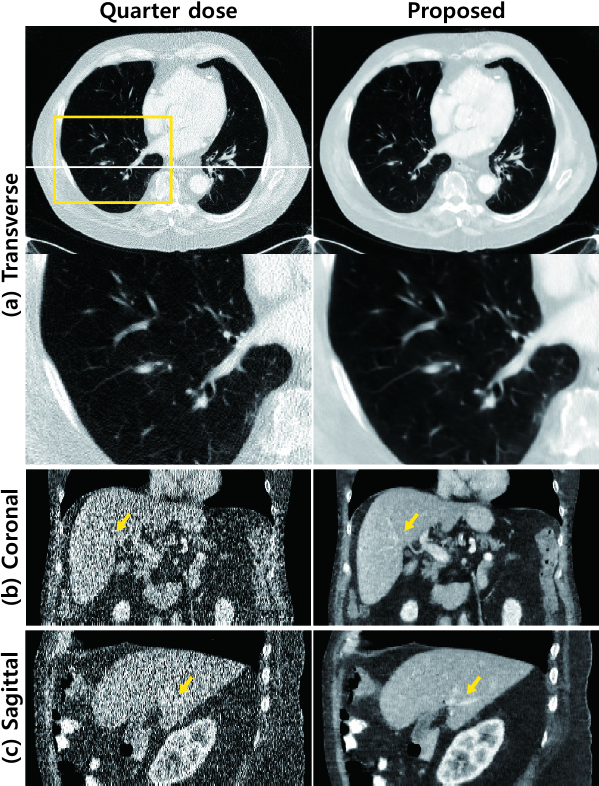

Figure 9: X-ray CT images from test data set ‘L057’. Quarter-dose images are in the first column and denoised images using the proposed algorithm are in the second column. (a) Transverse images. Enlarged images within the yellow box in the second row. The lesion is marked by red dashed circles. (b) Coronal images and (c) Sagittal images. Yellow arrow indicate the lesion. The intensity range was set to (-160,240) [HU] (Hounsfield unit).

Figure 10: X-ray CT images from test data set ‘L031’. Quarter-dose images are in the first column and denoised images using the proposed algorithm are in the second column. (a) Transverse images. Enlarged images within the yellow box in the second row. The intensity range has been adjusted to highlight the details of the lung. (b) Coronal images and (c) Sagittal images. Yellow arrows and circles indicate the details of the liver.

To demonstrate the detail preservation performance capabilities of the proposed network, we examine the results of another test data set, as shown in Fig. 10. The lung and other organs are visible in these images. The proposed network was able to describe the details of the lung structure. We also observed that the vessels in the liver are clearly reconstructed, as indicated by the yellow arrows in the coronal and sagittal presentation of the results.